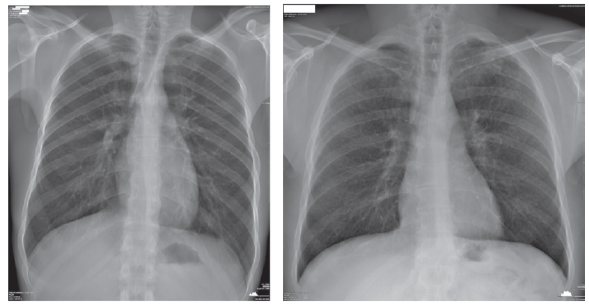

Obligatorias: Si la radiografía de tórax con técnica OIT muestra una profusión de 1/0 o 1/1, esto indica la presencia de opacidades pulmonares que sugieren la posibilidad de silicosis. Sin embargo, es importante tener en cuenta que la radiografía de tórax por sí sola no puede confirmar definitivamente el diagnóstico de silicosis, ya que existen otras condiciones pulmonares que pueden tener una apariencia similar en la radiografía47. Para una confirmación más precisa del diagnóstico, es recomendable que la lectura de la radiografía de tórax sea realizada por un lector acreditado o especialista en enfermedades pulmonares ocupacionales. Estos profesionales tienen la experiencia y los conocimientos necesarios para evaluar las imágenes radiográficas en el contexto de la exposición a sílice y las características clínicas del paciente48. El informe de lectura realizado por un lector acreditado proporcionará una evaluación detallada de la radiografía de tórax, identificando las opacidades presentes, su localización, tamaño y distribución49. Esto ayudará a determinar si los hallazgos son consistentes con la silicosis y a descartar otras enfermedades pulmonares similares. Ver gráfico 1, imagen 1. Es importante destacar que el diagnóstico definitivo de silicosis puede requerir una tomografía computarizada (TC) de tórax de alta resolución para confirmar el diagnóstico de silicosis50. Ver imagen 1, gráfico 1.

Imagen 1 Diferencia entre radiografía de tórax con técnica OIT en profusión 0/0 y 1/1. Imágenes gentiliza de reproducción del Dr. Anselmo López Guillén y Dr. Sergio Rovira Sans.

Gráfico 1 Guidelines for the Use of the ILO International Classification of Radiographs of Pneumoconioses» (Edición revisada 2022), es una herramienta importante utilizada por expertos en salud ocupacional para evaluar y clasificar radiografías de tórax en relación con las neumoconiosis, que son enfermedades pulmonares causadas por la inhalación de polvos y partículas en el lugar de trabajo.